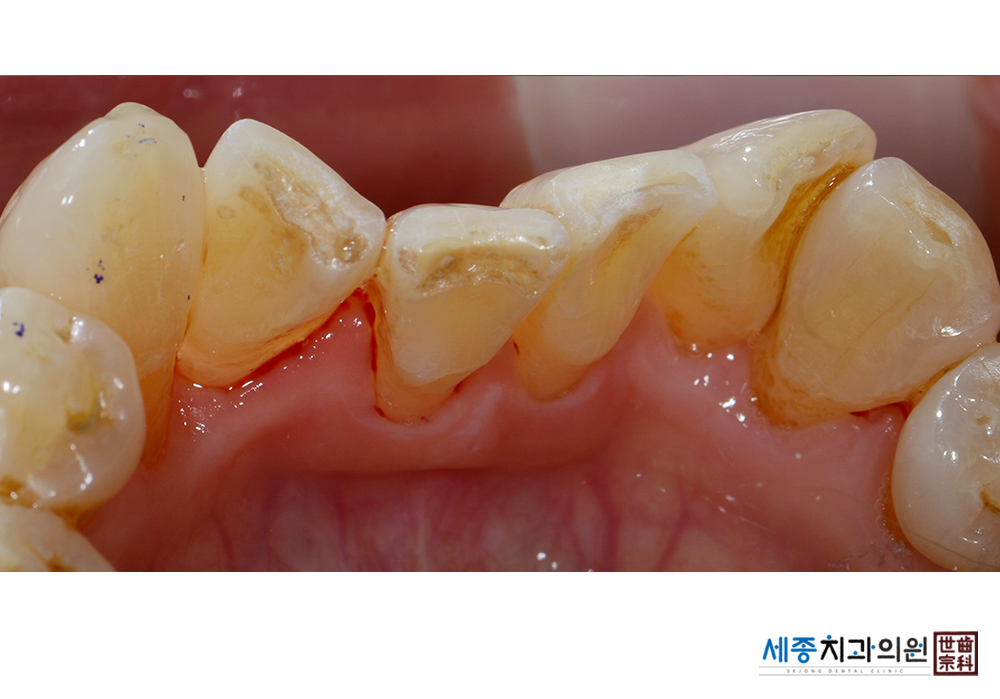

[스케일링] 치주질환 예방 스케일링

치료전 : 2021-05-13

가글마취&저주파 스켈러를 사용한 스케일링